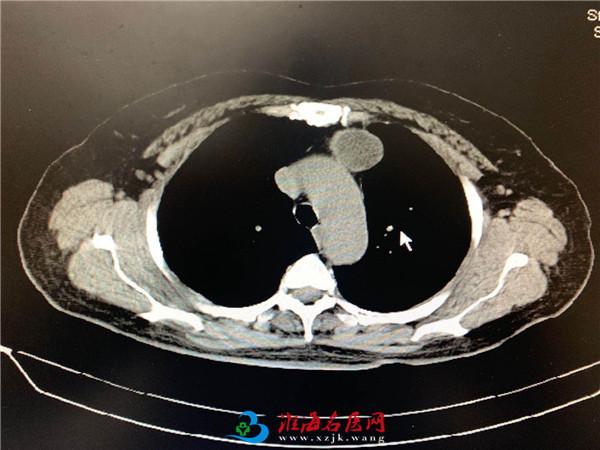

4月29日,心胸外科在麻醉科、手术室的帮助下顺利完成了3例达芬奇机器人辅助胸腔镜下胸部肿瘤切除术:第一例为一胸腺瘤患者,手术组经积极手术准备后,20分钟便完成肿瘤切除。第2例为一胸顶的巨大畸胎瘤,与无名静脉密切粘连,术中手术组充分发挥机器人的优势,在高倍放大视野下成功切除肿瘤,避免伤及血管与神经。第三例是位于食管与胸主动脉之间的囊肿,手术仅用时15分钟,便完整切除肿瘤,同时避免伤及食管与主动脉。这组手术的顺利完成充分发挥徐医附院达芬奇机器人手术的优势。